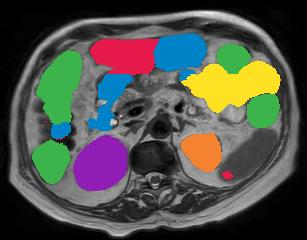

Vision transformers, with their ability to more efficiently model long-range context, have demonstrated impressive accuracy gains in several computer vision and medical image analysis tasks including segmentation. However, such methods need large labeled datasets for training, which is hard to obtain for medical image analysis. Self-supervised learning (SSL) has demonstrated success in medical image segmentation using convolutional networks. In this work, we developed a \underline{s}elf-distillation learning with \underline{m}asked \underline{i}mage modeling method to perform SSL for vision \underline{t}ransformers (SMIT) applied to 3D multi-organ segmentation from CT and MRI. Our contribution is a dense pixel-wise regression within masked patches called masked image prediction, which we combined with masked patch token distillation as pretext task to pre-train vision transformers. We show our approach is more accurate and requires fewer fine tuning datasets than other pretext tasks. Unlike prior medical image methods, which typically used image sets arising from disease sites and imaging modalities corresponding to the target tasks, we used 3,643 CT scans (602,708 images) arising from head and neck, lung, and kidney cancers as well as COVID-19 for pre-training and applied it to abdominal organs segmentation from MRI pancreatic cancer patients as well as publicly available 13 different abdominal organs segmentation from CT. Our method showed clear accuracy improvement (average DSC of 0.875 from MRI and 0.878 from CT) with reduced requirement for fine-tuning datasets over commonly used pretext tasks. Extensive comparisons against multiple current SSL methods were done. Code will be made available upon acceptance for publication.